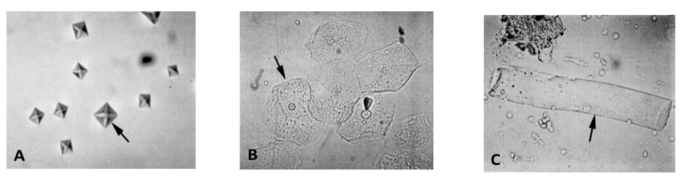

A urinálise fornece informações valiosas sobre o funcionamento do sistema urinário, sendo essencial sua realização no diagnóstico de muitas enfermidades. É composta por três exames: físico, químico e análise de sedimento. Considere as imagens abaixo, obtidas do sedimento urinário de um cão.

As figuras A, B e C representam, respectivamente,